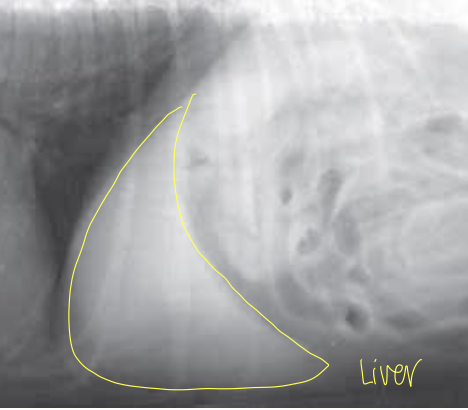

what is the larges organ/gland in the animal body?

liver

which organ is most cranial in the abdominal cavity?

liver

what organs is the liver between?

diaphragm and stomach

how is the liver oriented?

transversely

what type of dog is this?

barrel / short chested dog